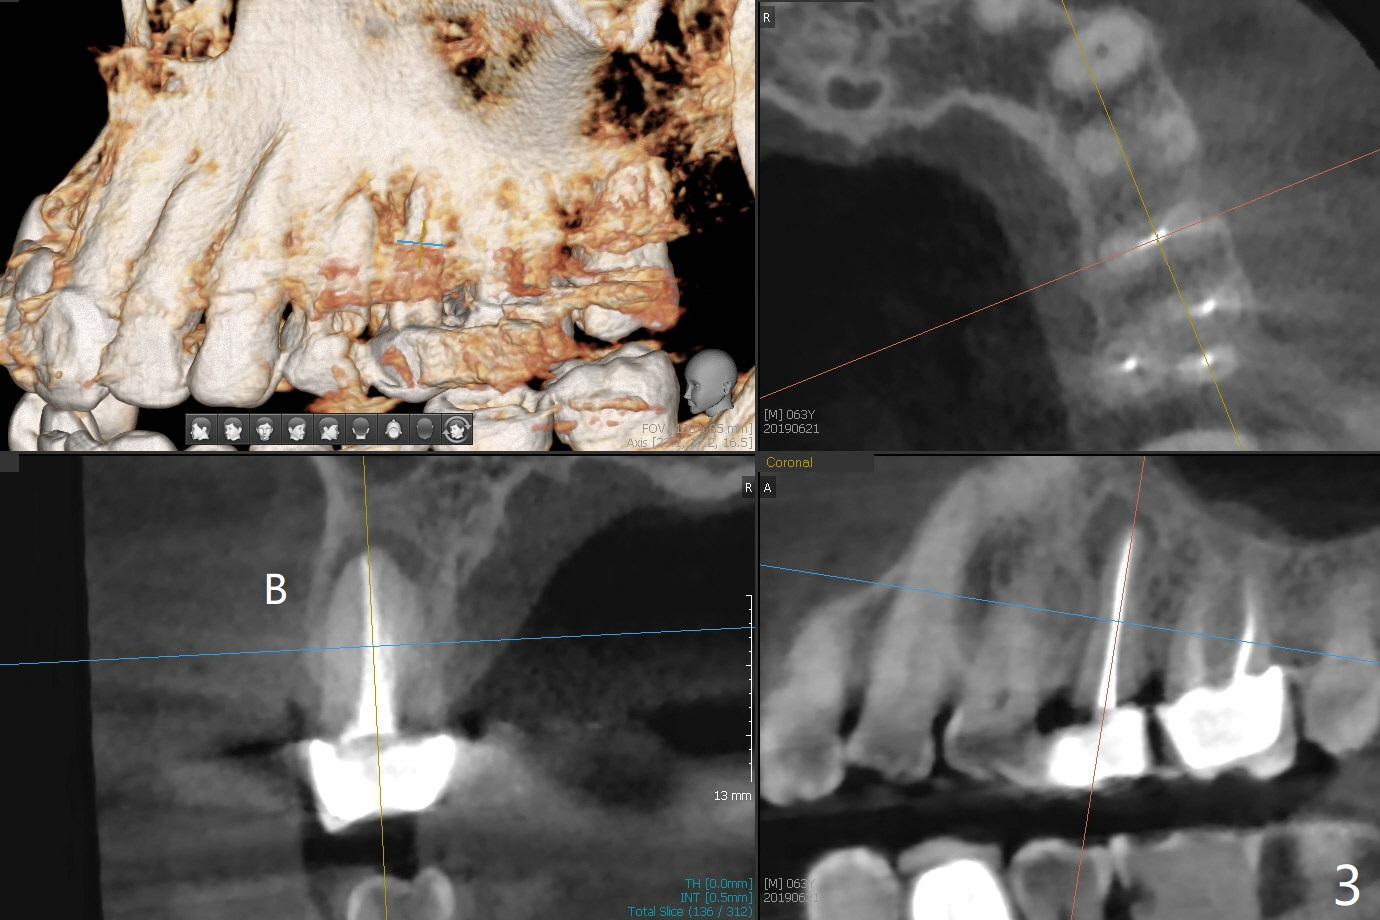

46岁男有多个修复物,左上第二前磨牙时常肿痛(13号牙),根尖阴影大(图一(CT一年前)箭头),根尖颊侧似乎折裂(图二箭头),颊侧牙槽嵴骨质仿佛存在(图三B),即刻种植可行(图四绿色),使用PRF膜(红色)和粘性骨块(黄色)同期修复颊侧骨板缺损。